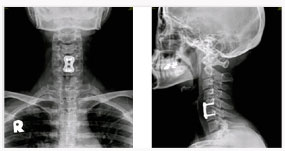

척추관 협착증의 방사선 소견